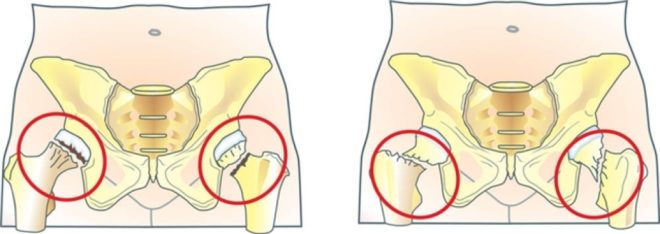

Amikor ilyen károsodás bekövetkezik szabotázs csőszerű csont. A lekerekített rész (fej) van csatlakoztatva a medence, törés következik be, és megköveteli egy sor intézkedést a gyors fellendüléshez és megakadályozza az esetleges szövődmények.

csípőtáji törés előfordulhat hatása alatt a mechanikai szilárdsága. Lehet, hogy egy baleset, esés a jégen, és így tovább. Sérülések ilyenfajta van minden korosztály, a csontokat a csípő sérülés lehet nyitott vagy zárt. Az első típus a törés több veszélyes, mert a csont jön ki, károsítja a lágy szövetek, a bőr.

- Sérülés esetén anélkül, elmozdulás, hiányában egyidejű komplikációk beteg egymásra gipsz, amelyet el kell távolítani csak két hónap után. Ez az időszak azonban változhat az egyedi körülményekhez.

- Ha a törés fragmenseket képződött, nem nélkülözheti a műtét és a „gyűjtő” csontok.

- Ha sérült a hip végtag általában természetellenesen kifordított, így a kár az ilyen nem lehet figyelmen kívül hagyni. Ennek oka az, hogy kiáll sérülés a közös a lábát.